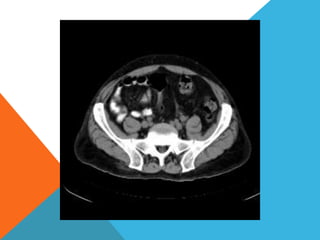

El paciente presentó síntomas de sangrado digestivo y pérdida de peso. Exámenes revelaron gastritis crónica asociada a H. pylori. Un tumor fue descubierto en una colonoscopia normal. La cirugía removió un tumor fibroide solitario, una rara neoplasia mesenquimal que usualmente crece lento y tiene bajo potencial de malignidad. El pronóstico después de la remoción quirúrgica es generalmente bueno.